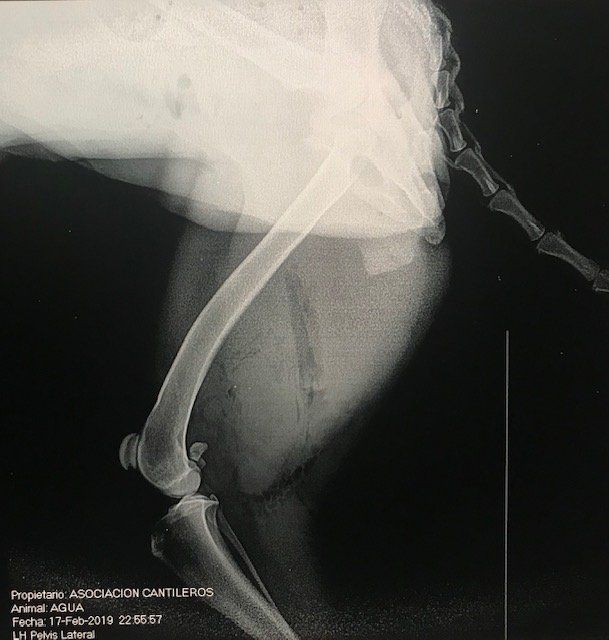

La estuvieron curando y la hicieron placas

Por suerte, al hacer las placas vieron que solo hera de la herida.

La primera es del torax, para descartar neumotorax u otros problemas, y la segunda de la zona afectada.

Como podeis ver en la placa, la herida es bastante profunda.